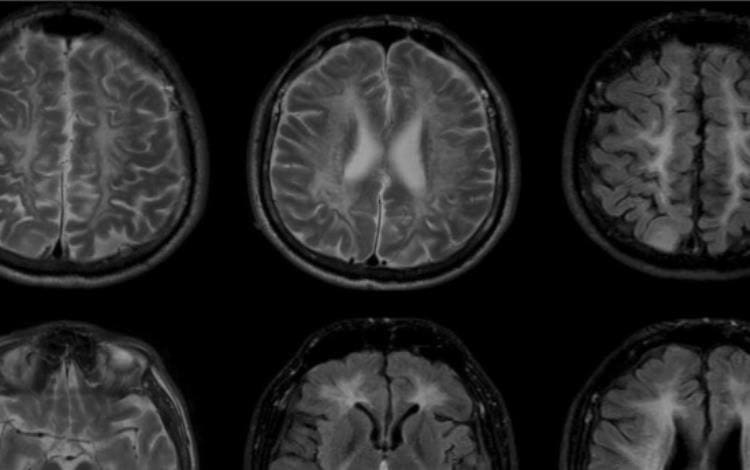

Ambos padecen el síndrome 4H, una enfermedad degenerativa que ha afectado su desarrollo físico y los ha dejado en condiciones de extrema vulnerabilidad.

El síndrome 4H es una enfermedad rara que afecta el crecimiento, el desarrollo neurológico y el sistema inmunológico. Los pacientes que la padecen suelen presentar discapacidad intelectual, retraso en el crecimiento y problemas de movilidad.